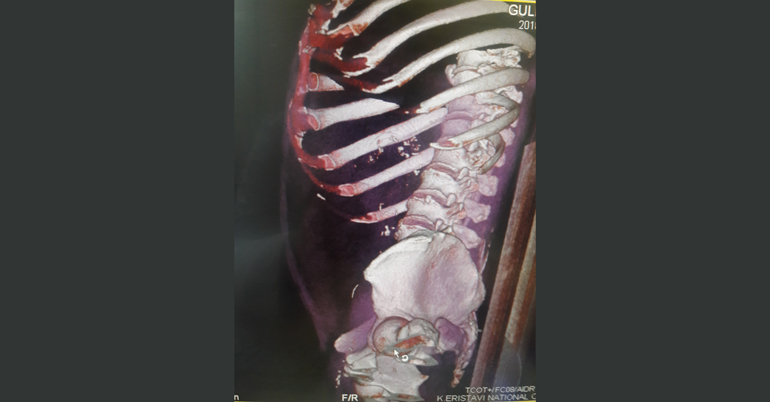

კლინიკის რადიოლოგმა ირაკლი გიგიაძემ შენიშნა, რომ წვრილი ნაწლავი უცხო სხეულით იყო დაზიანებული. დაუდგენელი სახეობის უცხო სხეული ნაწლავის სანათურიდან მუცლის ღრუში გამოდიოდა. პაციენტს ჩაუტარდა ლაპარასკოპია. მოიძებნა და ამოღებულ იქნა უცხო სხეული, ხოლო წვრილი ნაწლავის დაზიანებული უბანი გაიკერა.

უცხო სხეული, რომელიც ქირურგებმა პაციენტის წვრილი ნაწლავიდან ამოიღეს, აღმოჩნდა მეტალის მავთული (ჭურჭლის სახეხის შემადგენელი ნაწილი), რომლის ზომაც 4 სმ–ს შეადგენდა და კუჭ–ნაწლავში საკვებიდან მოხვდა.